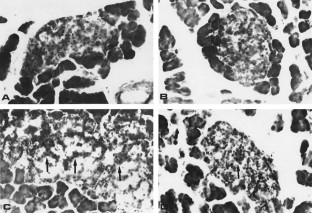

Figure 1